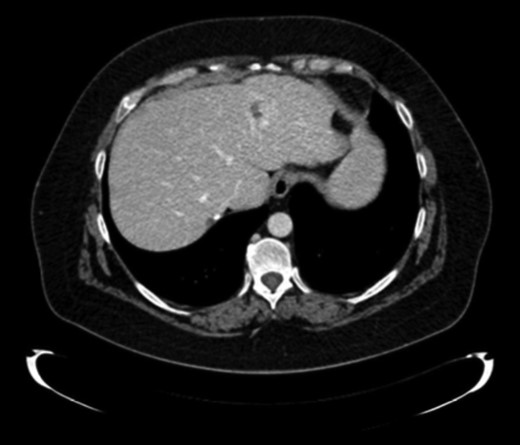

A new hepatic node in segment VII was observed nine months later (Fig. 3). Systemic treatment was administrated with cisplatin (75 mg/m2) and cetuximab for three months. At the end of the treatment, another non-anatomical metastasectomy with free margins was performed.